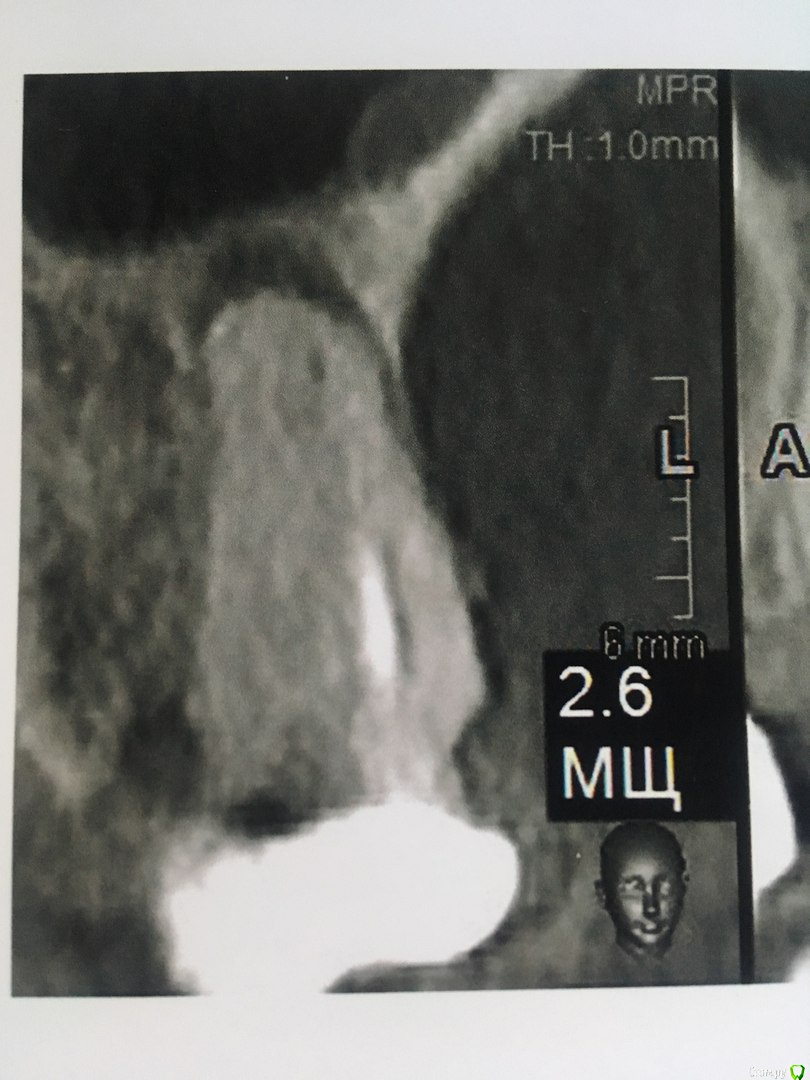

Добрый вечер!  Благодарю за ответ. Побывала у другого врача. Мнения разошлись. Второй доктор сказал 4,6  удаляем, а верхний 2,6 лечим.Первый же доктор сказал наоборот. Можно спросить еще Ваше мнение по 2,6 и 2,5 зубам?)

Добрый вечер! Спасибо Вам за ответ)   Можно так же узнать Ваше мнение по 2,6 и 2,5 зубкам (фото и описание КТ в сообщении выше).